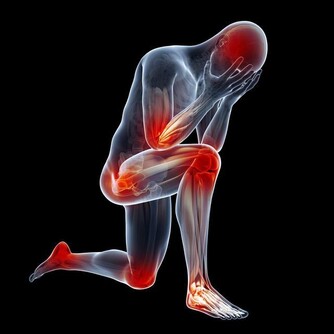

5、容易疲倦

肝在人體中也扮演著代謝器官的角色,像碳水化合物、蛋白質之類的物質都需要通過肝臟來進行代謝,如果肝功能不太好,就無法為身體提供足夠的能量,體力會產生明顯的下降,稍微做一些事情就會感到疲倦,完全無法集中精神。